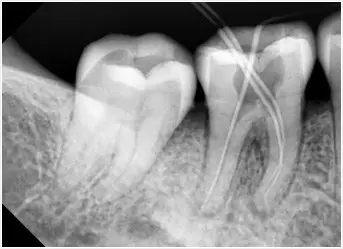

根管拍片確定情況

如果是齲壞比較嚴(yan) 重漏了牙神經,甚至發展為(wei) 根尖周炎了,那麽(me) 通常就需要先打開牙髓組織,封入牙髓失活劑讓牙神經失去活力。這時候封入的藥物叫做殺牙神經的藥物,如果快速殺牙神經可能2天就要更換藥物,而如果慢速殺牙神經一周。